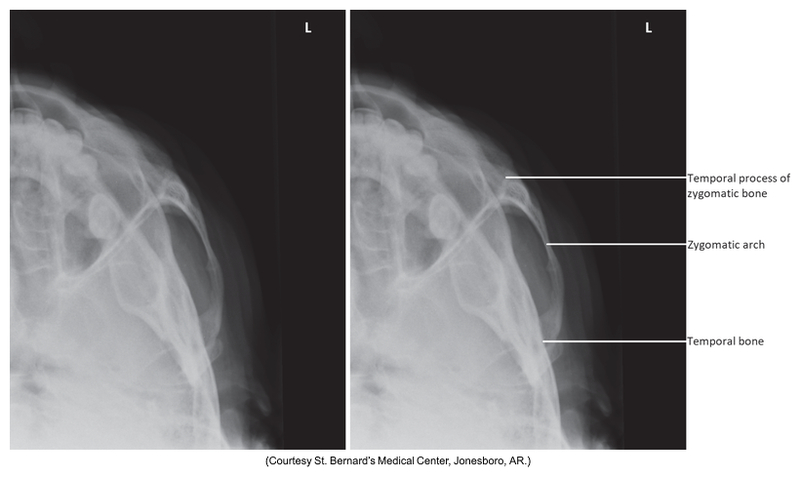

Tangential Projection of the zygomatic arch

Tangential of zygomatic arches